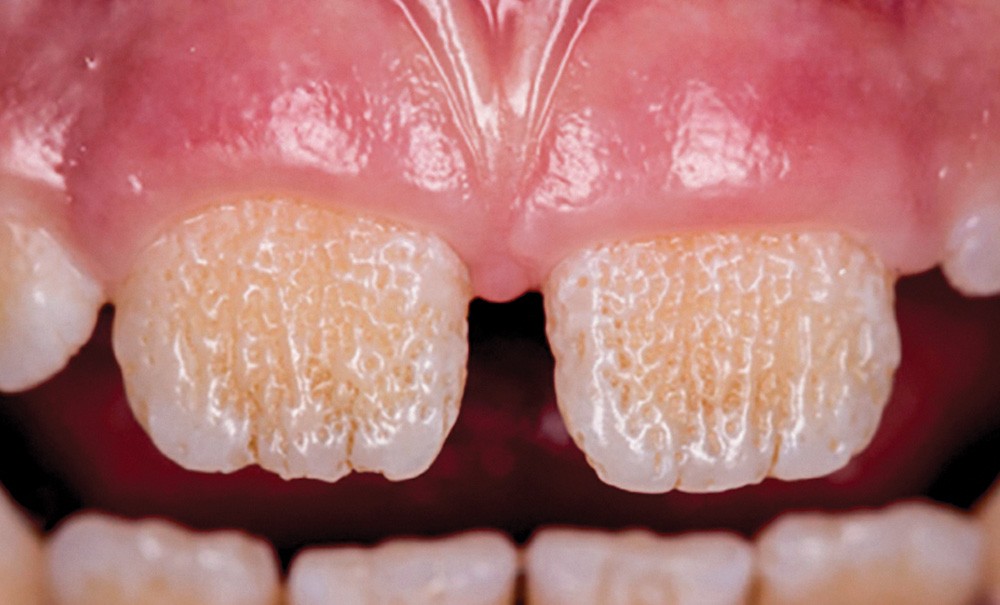

L’amélogenèse imparfaite est le nom donné à un groupe hétérogène de pathologies caractérisées par un défaut inné du développement de l’émail affectant toutes les dents des deux dentures. Ce sont des maladies génétiques dont l’origine est la mutation d’un gène impliqué dans l’amélogenèse. À ce jour, plus de 200 mutations différentes ont été identifiées, ce qui explique des phénotypes très variés [1]. Selon le stade de la maladie, l’émail est hypoplasique (défaut quantitatif), hypominéralisé, ou hypomature (défauts qualitatifs) : il est fin, fragile, tâché ou dyschromique. L’intensité des défauts peut être légère (forme frustre) ou très sévère, allant jusqu’à une absence totale d’émail. Son aspect est altéré par des dyschromies, fractures ou irrégularités de surface (fig. 1-4).